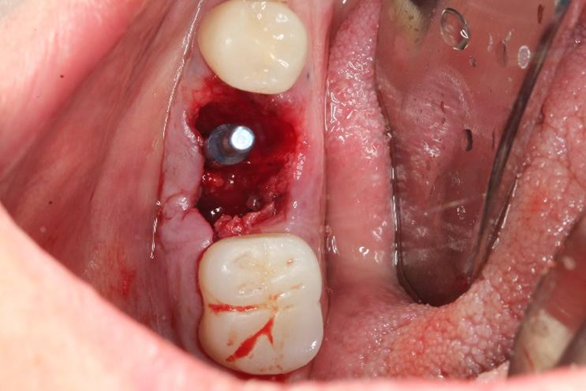

Uma paciente de 62 anos de idade apresentou-se com queixa de odor ruim na região do dente 46, pus, bolsa profunda e sangramento à sondagem. Os exames radiográficos evidenciaram lesão periapical, tratamento endodôntico e uma linha de fratura condenando a sobrevivência do elemento dentário 46. Assim, o elemento foi extraído e foi instalado um implante dentário de conexão interna morse no momento da exodontia. O mesmo foi estabilizado a 20Ncm e o parafuso de cobertura foi instalado. Em seguida, um biomaterial de origem bovina foi compactado no GAP e uma membrana não absorvível foi posicionada protegendo o biomaterial.

Após a análise clínica e tomográfica foi realizado o planejamento do caso: exodontia do dente 46 com a instalação imediata de um implante Cone Morse de corpo cônico (Maestro 4.0 X 9 – Implacil De Bortoli, São Paulo, Brasil), regeneração óssea guiada com biomaterial de origem bovina e colocação de uma barreira regenerativa não absorvível Cytoplast.